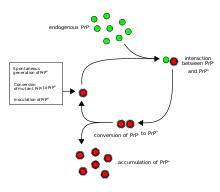

A prion /ˈpriːɒn/ ⓘ is a misfolded protein that can transmit its misfoldedness to normal variants of the same protein and trigger cellular death. Prions cause prion diseases known as transmissible spongiform encephalopathies (TSEs) that are transmissible, fatal neurodegenerative diseases in humans and animals.[3][4] The proteins may misfold sporadically, due to genetic mutations, or by exposure to an already misfolded protein.[5] The consequent abnormal three-dimensional structure confers on them the ability to cause misfolding of other proteins.

The first hypothesis that tried to explain how prions replicate in a protein-only manner was the heterodimer model.[52] This model assumed that a single PrPSc molecule binds to a single PrPC molecule and catalyzes its conversion into PrPSc. The two PrPSc molecules then come apart and can go on to convert more PrPC. However, a model of prion replication must explain both how prions propagate, and why their spontaneous appearance is so rare. Manfred Eigen showed that the heterodimer model requires PrPSc to be an extraordinarily effective catalyst, increasing the rate of the conversion reaction by a factor of around 1015.[53] This problem does not arise if PrPSc exists only in aggregated forms such as amyloid, where cooperativity may act as a barrier to spontaneous conversion. What is more, despite considerable effort, infectious monomeric PrPSc has never been isolated.

An alternative model assumes that PrPSc exists only as fibrils, and that fibril ends bind PrPC and convert it into PrPSc. If this were all, then the quantity of prions would increase linearly, forming ever longer fibrils. But exponential growth of both PrPSc and of the quantity of infectious particles is observed during prion disease.[54][55][56] This can be explained by taking into account fibril breakage.[57] A mathematical solution for the exponential growth rate resulting from the combination of fibril growth and fibril breakage has been found.[58] The exponential growth rate depends largely on the square root of the PrPC concentration.[58] The incubation period is determined by the exponential growth rate, and in vivo data on prion diseases in transgenic mice match this prediction.[58] The same square root dependence is also seen in vitro in experiments with a variety of different amyloid proteins.[59]

Until 2015 all known mammalian prion diseases were considered to be caused by the prion protein, PrP; in 2015 multiple system atrophy was found to be transmissible and was hypothesized to be caused by a new prion, the misfolded form of a protein called alpha-synuclein.[10] The endogenous, properly folded form of the prion protein is denoted PrPC (for Common or Cellular), whereas the disease-linked, misfolded form is denoted PrPSc (for Scrapie), after one of the diseases first linked to prions and neurodegeneration.[35][16] The precise structure of the prion is not known, though they can be formed spontaneously by combining PrPC, homopolymeric polyadenylic acid, and lipids in a protein misfolding cyclic amplification (PMCA) reaction even in the absence of pre-existing infectious prions.[61] This result is further evidence that prion replication does not require genetic information.[78]

Transmission

It has been recognized that prion diseases can arise in three different ways: acquired, familial, or sporadic.[79] It is often assumed that the diseased form directly interacts with the normal form to make it rearrange its structure. One idea, the "Protein X" hypothesis, is that an as-yet unidentified cellular protein (Protein X) enables the conversion of PrPC to PrPSc by bringing a molecule of each of the two together into a complex.[80]